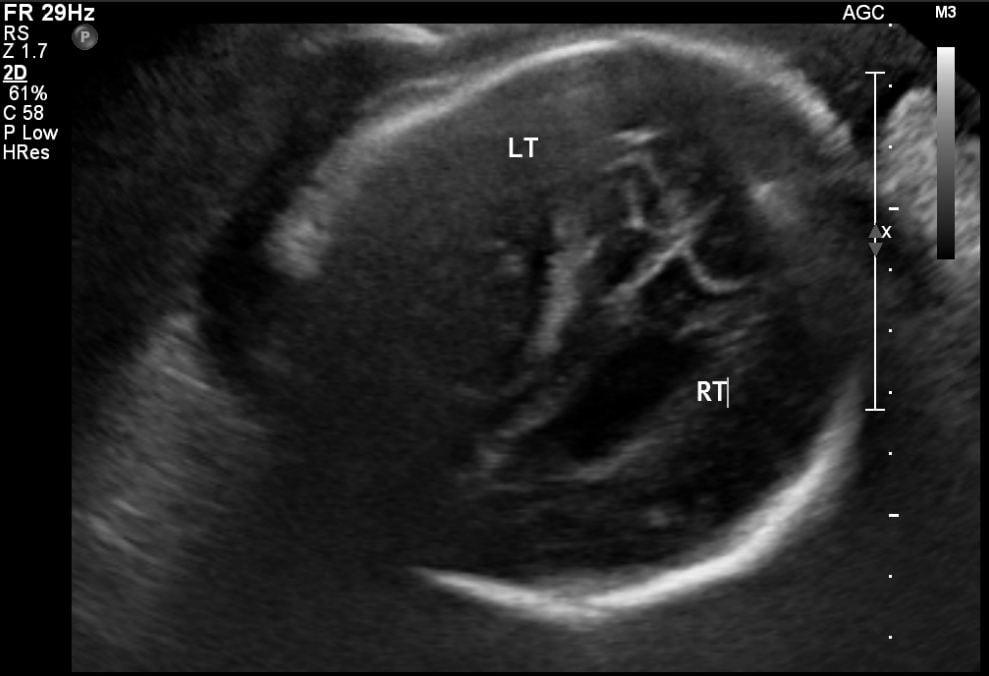

Learn how to effectively assess and diagnose congenital Cytomegalovirus (CMV) through sonography. This course covers essential sonographic signs, including ventriculomegaly, calcifications, and other fetal abnormalities associated with CMV. Gain insights into prenatal and postnatal treatment options, and understand the role of ultrasound in detecting this common in-utero infection.

Identify the sonographic signs and treatment of congenital CMV.